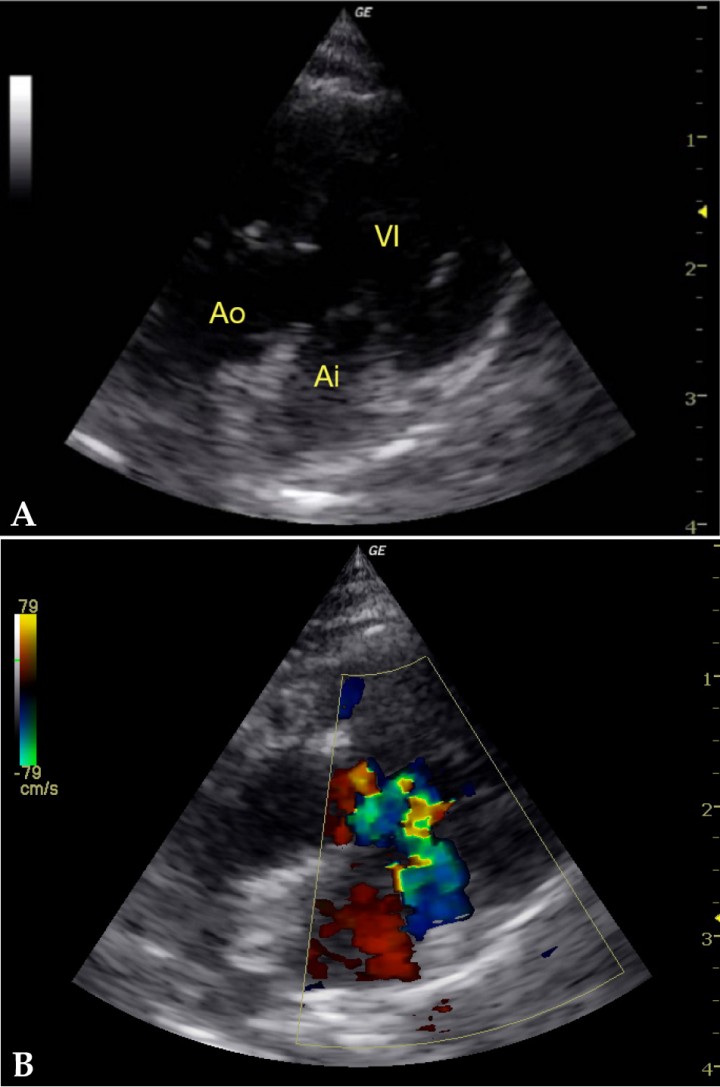

Una vez estabilizado el paciente, se realiza una ecocardiografía para confirmar el origen cardíaco de los signos clínicos. El abordaje por el lado derecho no permite localizar el corazón. Se sospecha de una localización anómala del mismo en la caja torácica. Se aborda el corazón solo por el lado izquierdo. Aunque por motivos anatómicos no se logra una idónea optimización de las vistas, es posible observar:

• Engrosamiento moderado difuso y homogéneo (6,5 mm medido en 2D) de las paredes del ventrículo izquierdo (Fig. 2A) en corte apical 5 cámaras.

• Presencia de flujo turbulento en el tracto de salida izquierdo con aumento de la velocidad en grado leve (2,2 m/s) simultáneo a insuficiencia mitral (Fig. 2B), lo que permite el diagnóstico de SAM (Systolic Anterior Movement) de la válvula mitral. El tejido endocárdico de esta región se presenta hiperecógeno, compatible con fibrosis.

• No se observa dilatación del atrio izquierdo.

• Flujo transmitral de relajación anómala: inversión del flujo E/A con ratio E/A 0,5, lo que sugiere una disfunción diastólica de grado 1.[ Boon J. Veterinary echocardiography. 2nd edition. Chapter 4; p:287-296. 2011. Wiley-Blackwell. Ames, Iowa, USA. ]

<p>Imagen de ecocardiografía. (<strong>A</strong>) Corte apical 5 cámaras lado izquierdo con escasa alineación por desituación del corazón en la caja torácica que muestra engrosamiento difuso de las paredes ventriculares. (<strong>B</strong>) Corte apical 5 cámaras lado izquierdo con Doppler color que muestra la presencia de obstrucción dinámica del tracto de salida izquierdo con movimiento sistólico anterior de la válvula mitral. AI: aurícula izquierda, VI: ventrículo izquierdo, Ao: aorta.</p>

Imagen de ecocardiografía. (A) Corte apical 5 cámaras lado izquierdo con escasa alineación por desituación del corazón en la caja torácica que muestra engrosamiento difuso de las paredes ventriculares. (B) Corte apical 5 cámaras lado izquierdo con Doppler color que muestra la presencia de obstrucción dinámica del tracto de salida izquierdo con movimiento sistólico anterior de la válvula mitral. AI: aurícula izquierda, VI: ventrículo izquierdo, Ao: aorta.

Con estos hallazgos, se diagnostica cardiomiopatía hipertrófica obstructiva con disfunción diastólica de grado 1. Se considera poco probable la enfermedad cardíaca como causante de los signos clínicos y radiográficos.